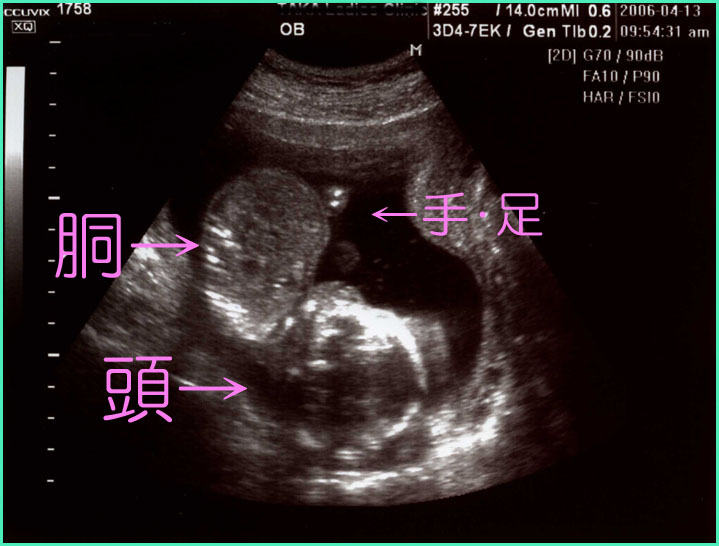

2dエコー Instagram Posts Gramho Com

妊娠28週目 28w0d 6d のエコー写真とエピソード 妊娠8ヶ月 Cozre コズレ 子育てマガジン

妊娠30週6日 30w6d の超音波 エコー 写真

妊娠28週目 28w0d 6d のエコー写真とエピソード 妊娠8ヶ月 Cozre コズレ 子育てマガジン

妊娠28週目 28w0d 6d のエコー写真とエピソード 妊娠8ヶ月 Cozre コズレ 子育てマガジン

妊娠28週目 28w0d 6d のエコー写真とエピソード 妊娠8ヶ月 Cozre コズレ 子育てマガジン

妊娠28週目 28w0d 6d のエコー写真とエピソード 妊娠8ヶ月 Cozre コズレ 子育てマガジン

妊娠30週6日 30w6d の超音波 エコー 写真

妊娠30週6日 30w6d の超音波 エコー 写真

妊娠30週6日 30w6d の超音波 エコー 写真

妊娠30週6日 30w6d の超音波 エコー 写真

妊娠28週目 28w0d 6d のエコー写真とエピソード 妊娠8ヶ月 Cozre コズレ 子育てマガジン

妊娠28週目 28w0d 6d のエコー写真とエピソード 妊娠8ヶ月 Cozre コズレ 子育てマガジン

妊娠28週目 28w0d 6d のエコー写真とエピソード 妊娠8ヶ月 Cozre コズレ 子育てマガジン

妊娠28週目 28w0d 6d のエコー写真とエピソード 妊娠8ヶ月 Cozre コズレ 子育てマガジン

妊娠28週目 28w0d 6d のエコー写真とエピソード 妊娠8ヶ月 Cozre コズレ 子育てマガジン

妊娠28週目 28w0d 6d のエコー写真とエピソード 妊娠8ヶ月 Cozre コズレ 子育てマガジン

妊娠23週4日 23w4d の超音波 エコー 写真

妊娠28週目 28w0d 6d のエコー写真とエピソード 妊娠8ヶ月 Cozre コズレ 子育てマガジン

妊娠28週目 28w0d 6d のエコー写真とエピソード 妊娠8ヶ月 Cozre コズレ 子育てマガジン